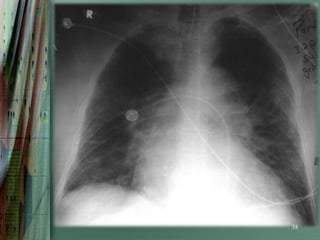

Radiography

Chest radiography is helpful in distinguishing CPE from other

pulmonary causes of severe dyspnea.

Features that suggest CPE rather than NCPE and other lung

pathologies include the following:

•   Enlarged heart

•   Inverted blood flow

•   Kerley lines

•   Basilar edema (vs diffuse edema)

•   Absence of air bronchograms

•   Presence of pleural effusion (particularly bilateral and

36

symmetrical pleural effusions)

37

38